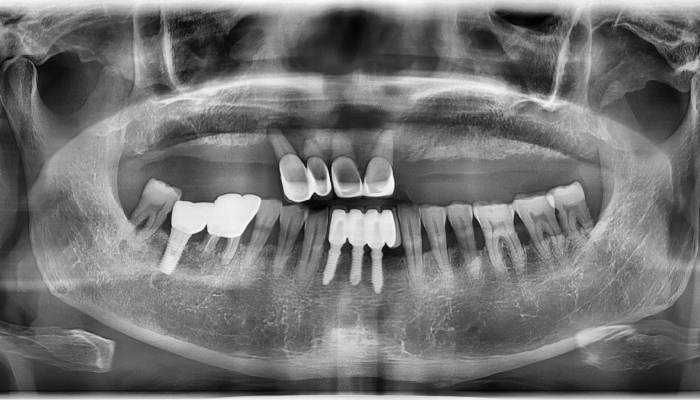

뼈이식 임플란트 전후 사례

• 식립전

식립후